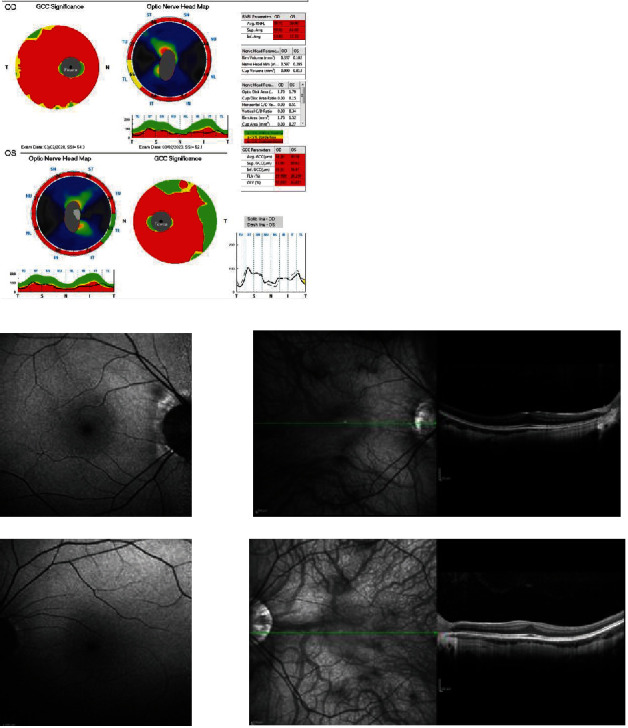

Objective: We describe a patient affected by congenital stationary night blindness (CSNB) secondary to CACNA1F and optic neuropathy associated with an AFG3L2 variant. Methods: We performed comprehensive neuro-ophthalmologic examinations, retinal imaging, complete ocular electrophysiology, and brain and optic nerve MRI. Genomic DNA was extracted from the peripheral blood. The patient's DNA was then investigated by next-generation sequencing (NGS) with a panel including 32 genes associated with retinal dystrophy and therefore with a panel including seven genes associated with genetic forms of optic atrophy. Results: The genetic analysis identified a pathogenetic CACNA1F variant causing CSNB and a heterozygous variant in AFG3L2 that alters OPA1 processing and is known to be associated with OPA1-like optic neuropathy. Conclusion: Optic disc atrophy has been previously described as an atypical feature in the phenotype of CSNB CACNA1F-related. In this patient, we found a variant of the AFG3L2 gene that presumably explains the presence of optic atrophy in a subject affected by CSNB. Clinical Relevance: The clinical evidence of optic atrophy, which is atypical in CSNB, should raise the suspicion of concomitant hereditary optic neuropathy and emphasize the importance of broad genetic diagnostic testing to better define the genotype-phenotype correlation.

Abstract Image